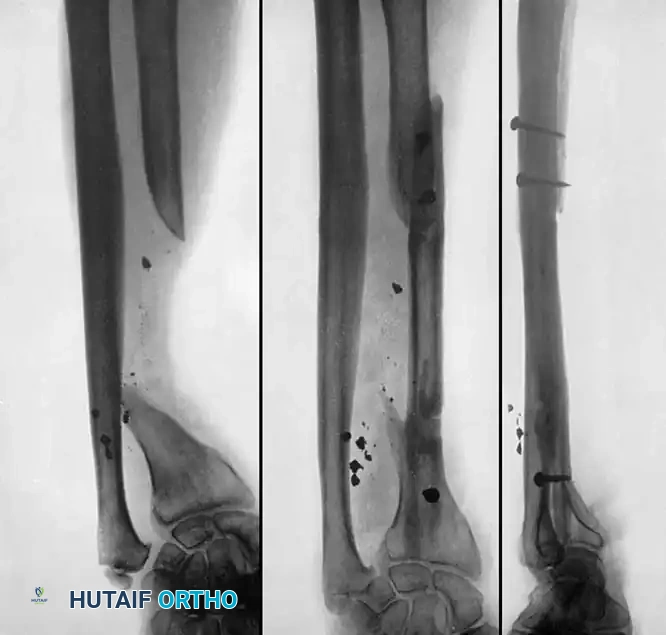

Associated Surgical & Radiographic Imaging